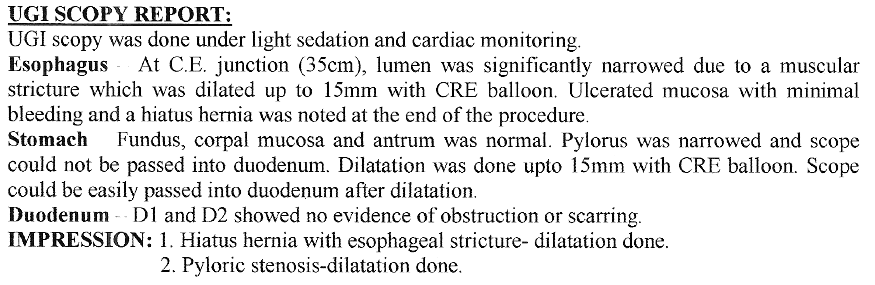

Achalasia Cardia - Balloon Dilatation

Achalasia Cardia - Balloon Dilatation

Achalasia Cardia - Balloon Dilatation

Achalasia Cardia - Balloon Dilatation